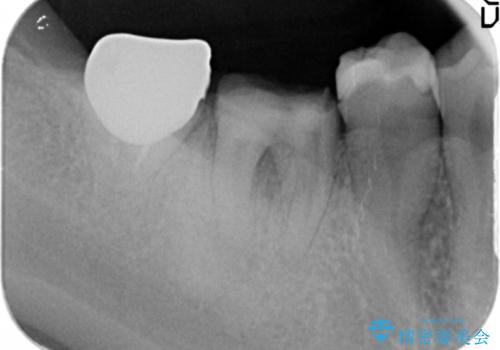

- 銀歯が取れてしまい、治療を希望され来院されました。

歯には大きな穴が開き、虫歯も大きくなってしまい残すことが難しいような状況であったため抜歯を余儀なくされました。

抜歯後はセラミックブリッジを用いた咬合機能回復を計画します。